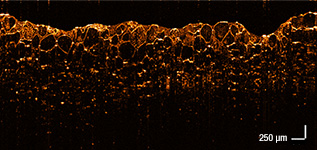

Application Examples

In Vivo

Small Animal

Biology

Mouse Lung

Retina Cone Cells